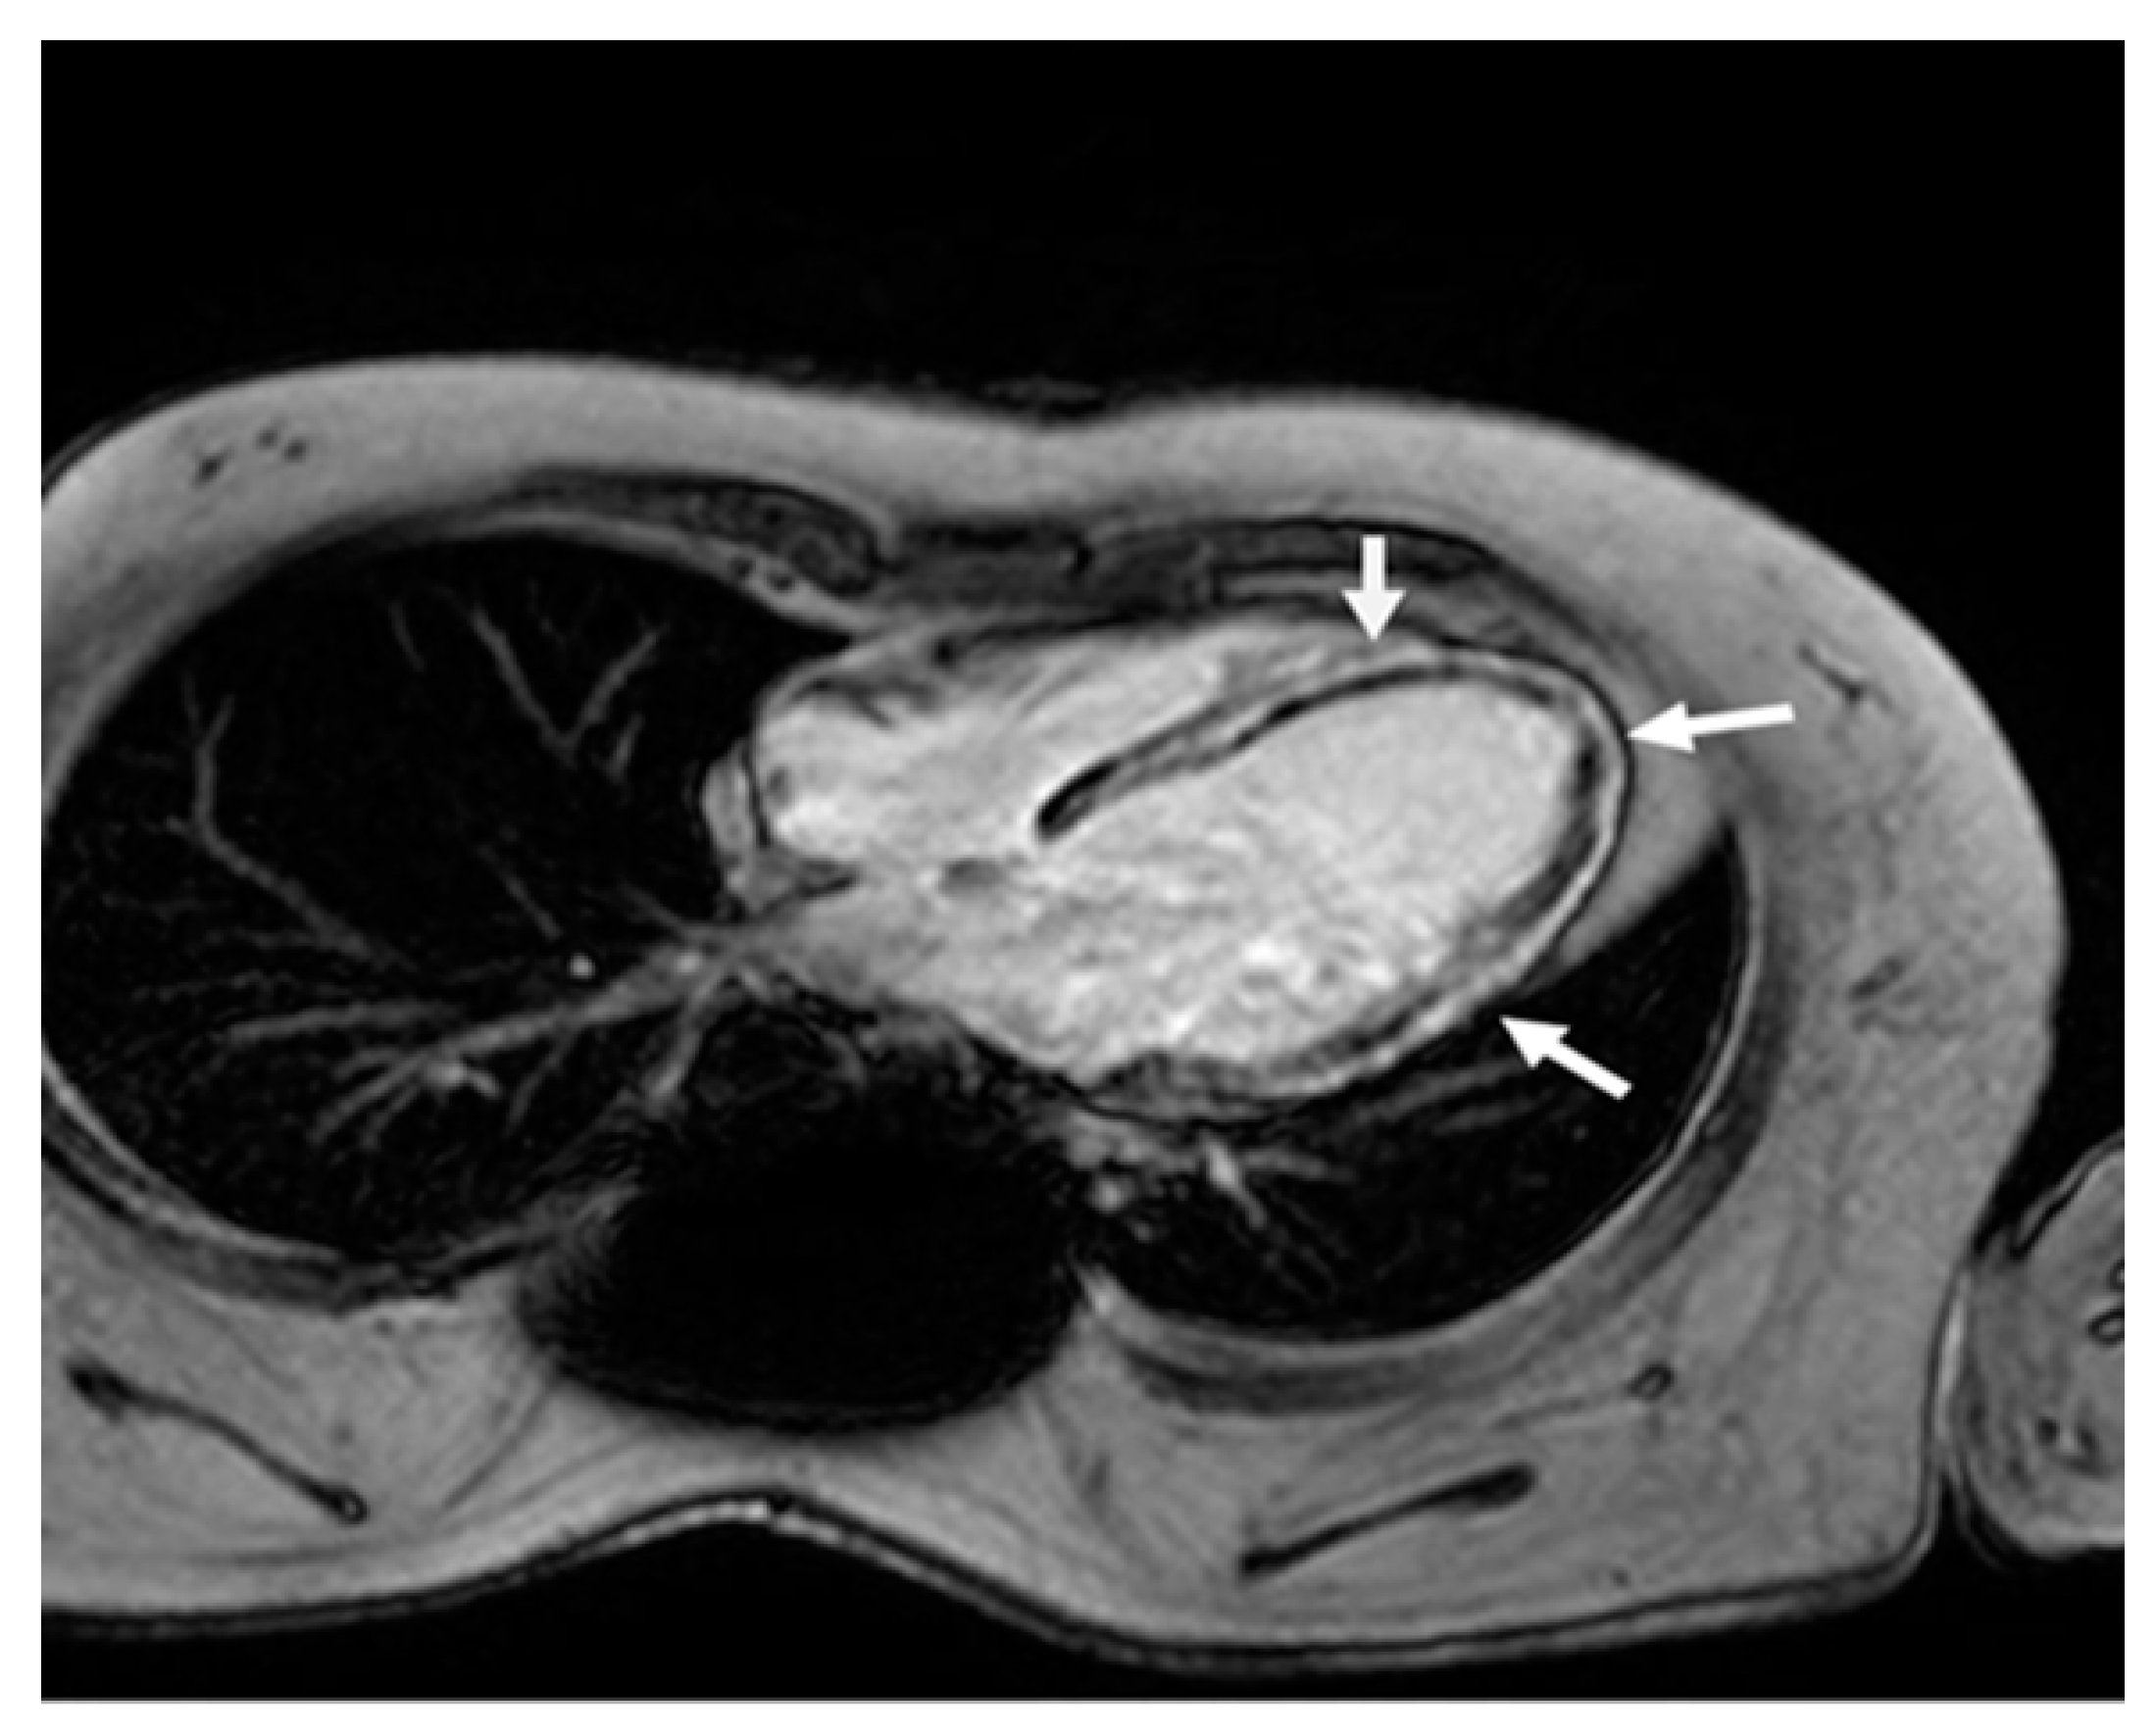

| CMR | Extensive fibrosis |

| CRM | Severe fibrosis |